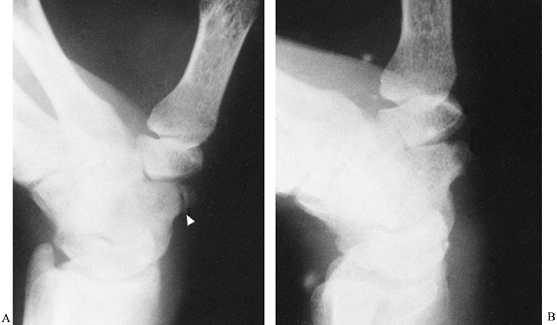

![]() |

Figure 42.6. A: Fracture of a scaphoid tubercle (arrowhead). B: The fracture healed after 6 weeks of immobilization.